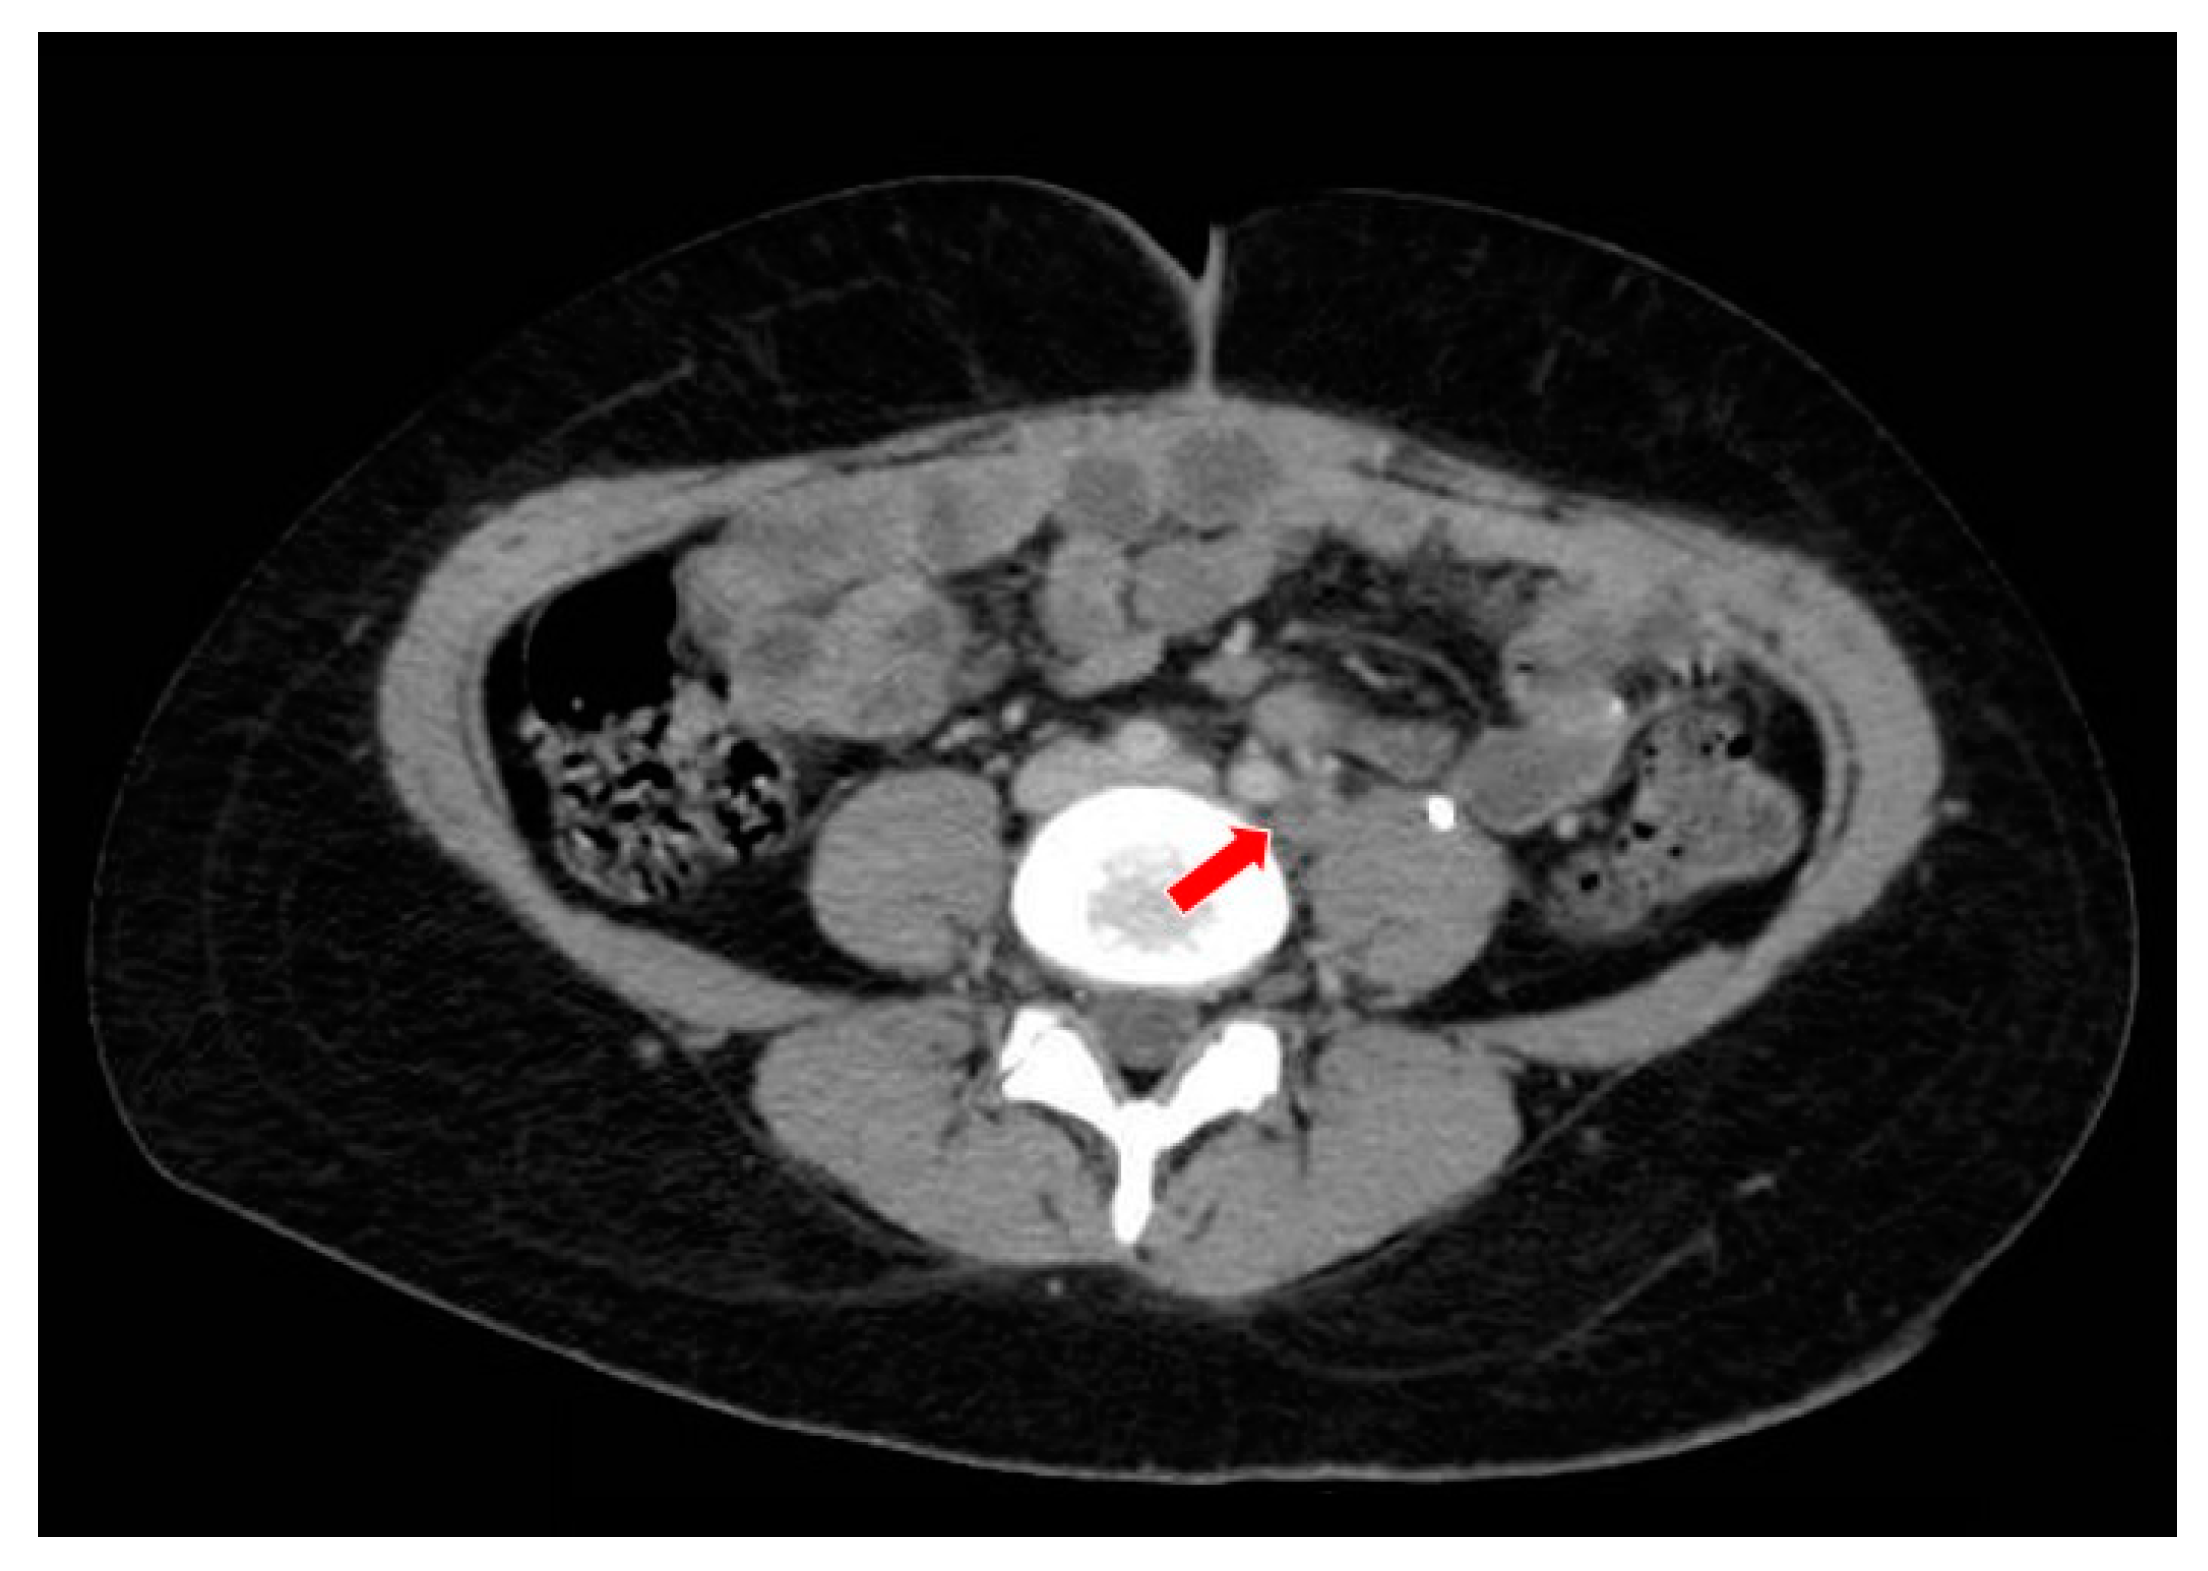

2. Case Report